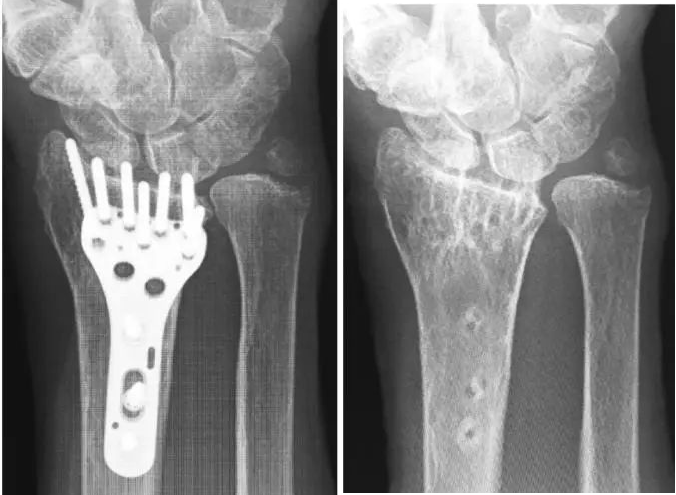

# تقنيات مبتكرة لتثبيت كسور نهاية عظم الكعبرة باستخدام الصفائح الراحية: دليل جراحي متكامل تُعتبر كسور نهاية عظم الكعبرة…